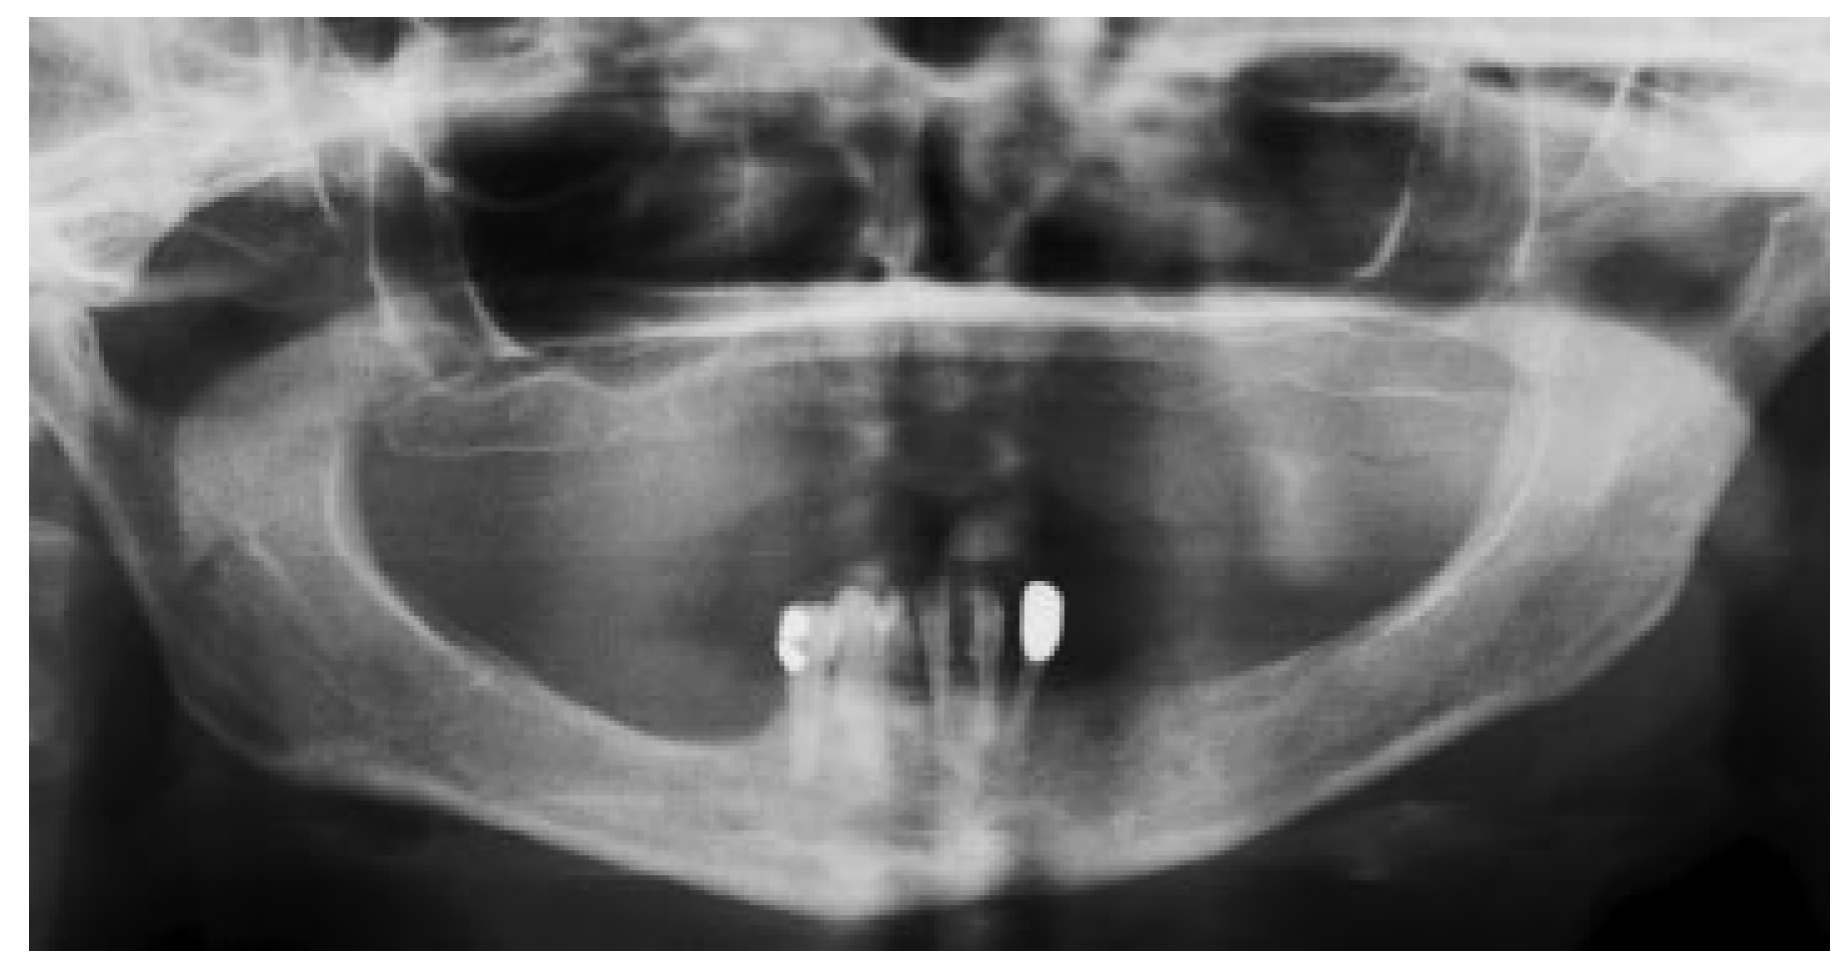

Clinical Report

Figure 2. Preoperative orthopantomogram showing atrophic posterior mandible.